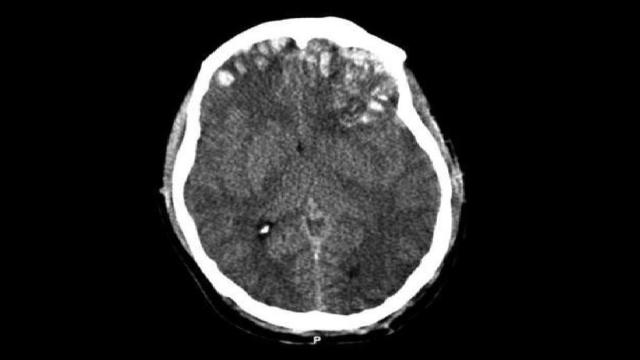

El traumatismo craneal de Ángel Nieto: difícil pronóstico y qué hacer Roberto Méndez 26/07/2017 20:11h

Ángel Nieto sufre un fuerte traumatismo craneal y tiene un coágulo en la cabeza Elena Isardo 26/07/2017 18:43h